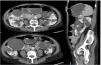

Se trata de una mujer de 69 años, con antecedentes de hipertensión, polineuropatía sensitiva axonal por síndrome CANVAS y PQRAD diagnosticada a los 40años, con confirmación posterior de mutación en PKD2. A lo largo de la evolución de la enfermedad han destacado las siguientes incidencias: punción evacuadora de los quistes que comprimían la arteria renal hace aproximadamente 30años y varios episodios de pseudo-obstrucción intestinal justificados por un megacolon adquirido secundario a compresión intestinal por los quistes renales (fig. 1) que precisaron la punción y la esclerosis de un quiste dominante de gran tamaño en el último año. A pesar de ello, la paciente persistió con dificultad para la ingesta y dolor abdominal. En ese momento la función renal se mantenía normal y no presentaba criterios de rápida progresión, lo que impedía el uso de tolvaptán según las actuales indicaciones. Sin embargo, en septiembre de 2022 se decidió ensayar tratamiento compasivo con tolvaptán de acuerdo con la paciente, con fines dirigidos a disminuir el volumen abdominal, así como un mejor control del dolor. En consonancia con este razonamiento, se prescribieron 45mg de tolvaptán por la mañana y 15mg ocho horas después.